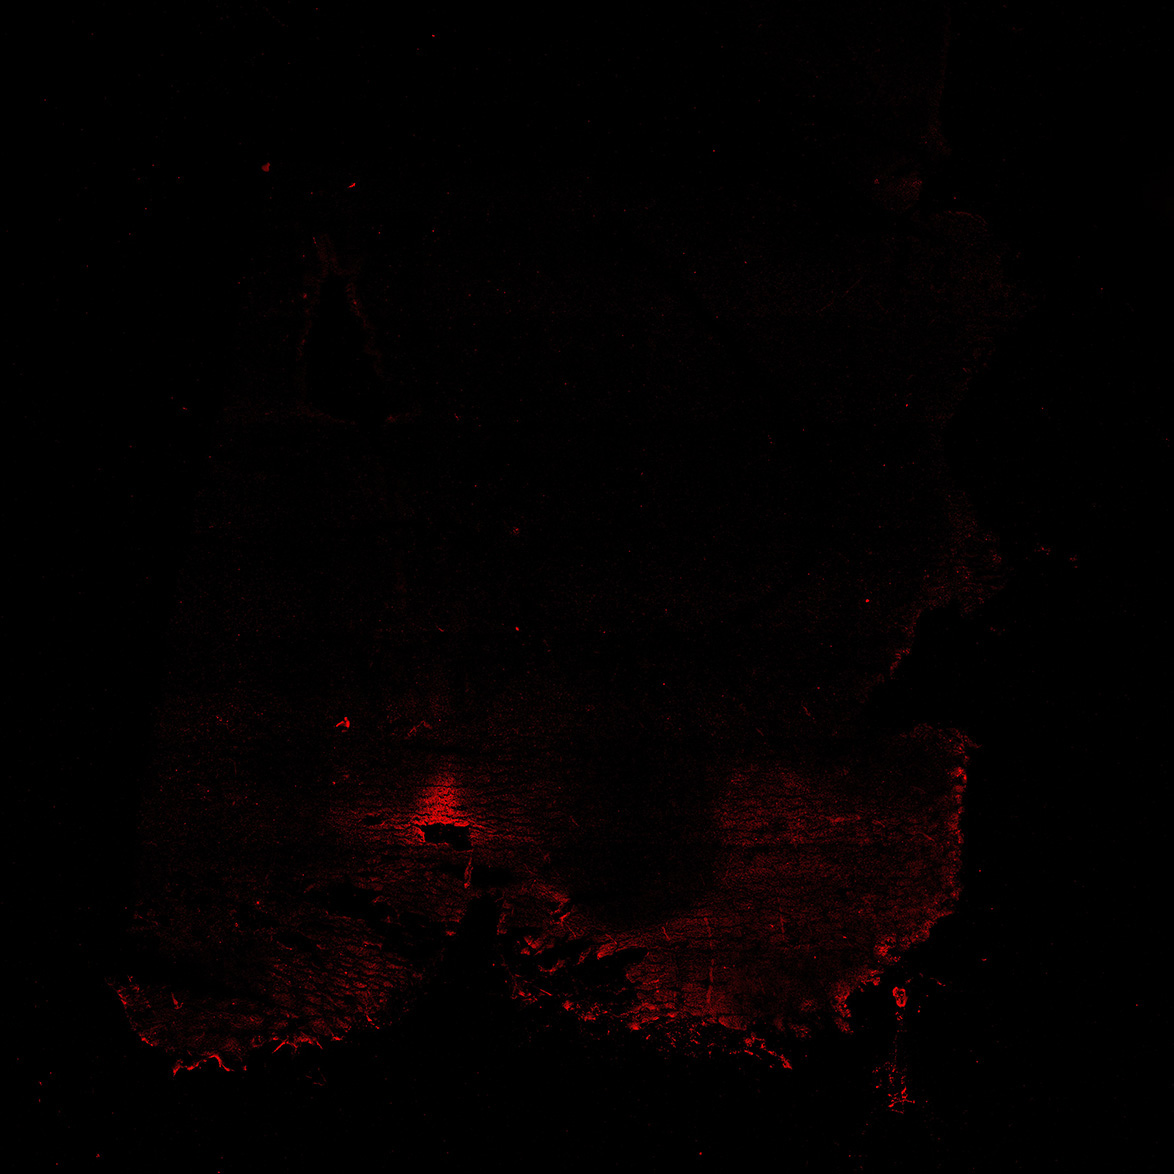

TH

11PCW human midbrain